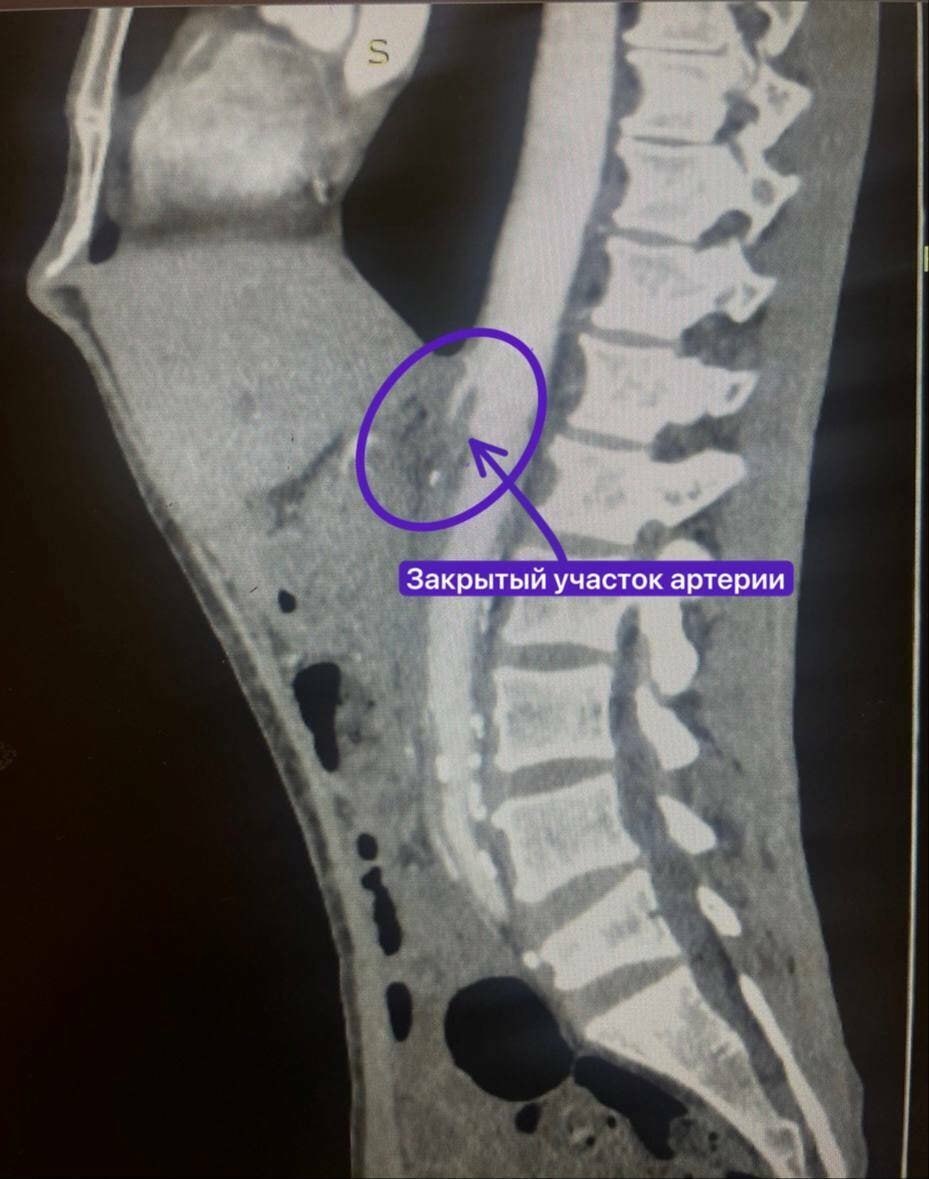

У мужчины из-за атеросклероза бляшки закрыли верхнюю брыжеечную артерию. Обычно в таких случаях в артерию под контролем рентгена хирурги ставят стент.

Из-за того, что артерия закрылась совсем, рентген-хирурги не смогли провести через нее проводником. Мужчину перевели в сосудистое отделение, где хирурги взялись за протезирование артерии.

Заведующий отделением Рифкат Нуретдинов и сосудистый хирург Михаил Андреев подшили полимерный протез от аорты к верхней брыжеечной артерии, тем самым восстановив кровоток в закрытой артерии.